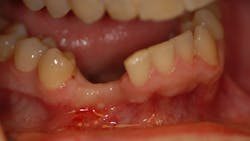

A 37-year-old male presents with a history of trauma to the anterior mandible. At the time of the incident, teeth Nos. 26 and 27 were extracted without ridge preservation. The patient was left with large crestal and buccal defects postextraction (figures 1 and 2).